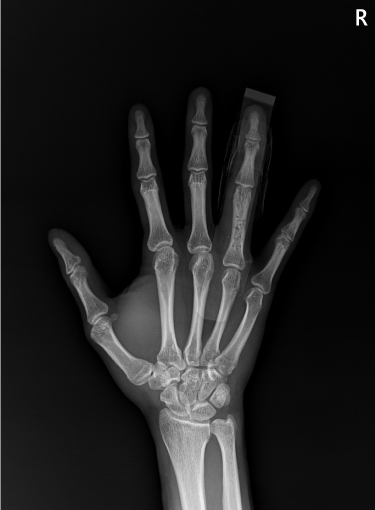

손가락 골절

2022.11.23

2023.03.17

손목 골절

2023.01.04

2023.03.20